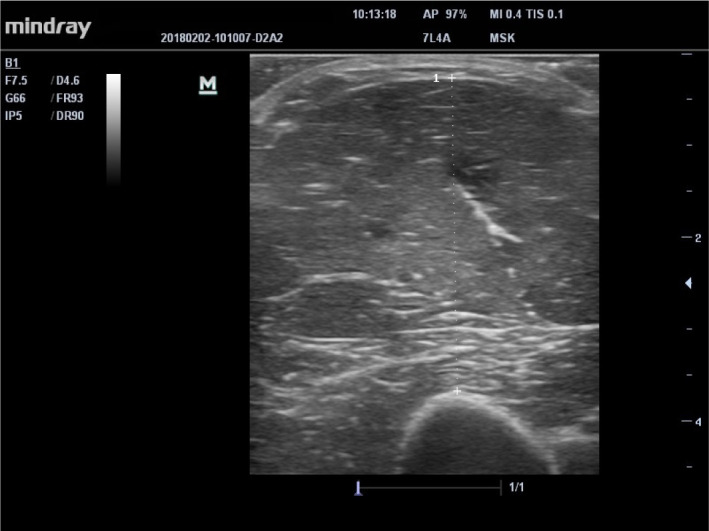

Methods: Twenty-two FMS patients and 18 asymptomatic control cases who applied to the physical medicine and rehabilitation outpatient clinic were included. The thickness of the gastrocnemius medialis/lateralis, trapezius, and upper arm muscle was evaluated with ultrasonography. Muscle strength was evaluated with hand grip strength, muscle performance with chair stand test (CST), walking performance with 10 m walking test, disease severity with Fibromyalgia Impact Questionnaire-Revised, pain severity with VAS, and kinesiophobia with TAMPA kinesiophobia scale.

Abstract Image